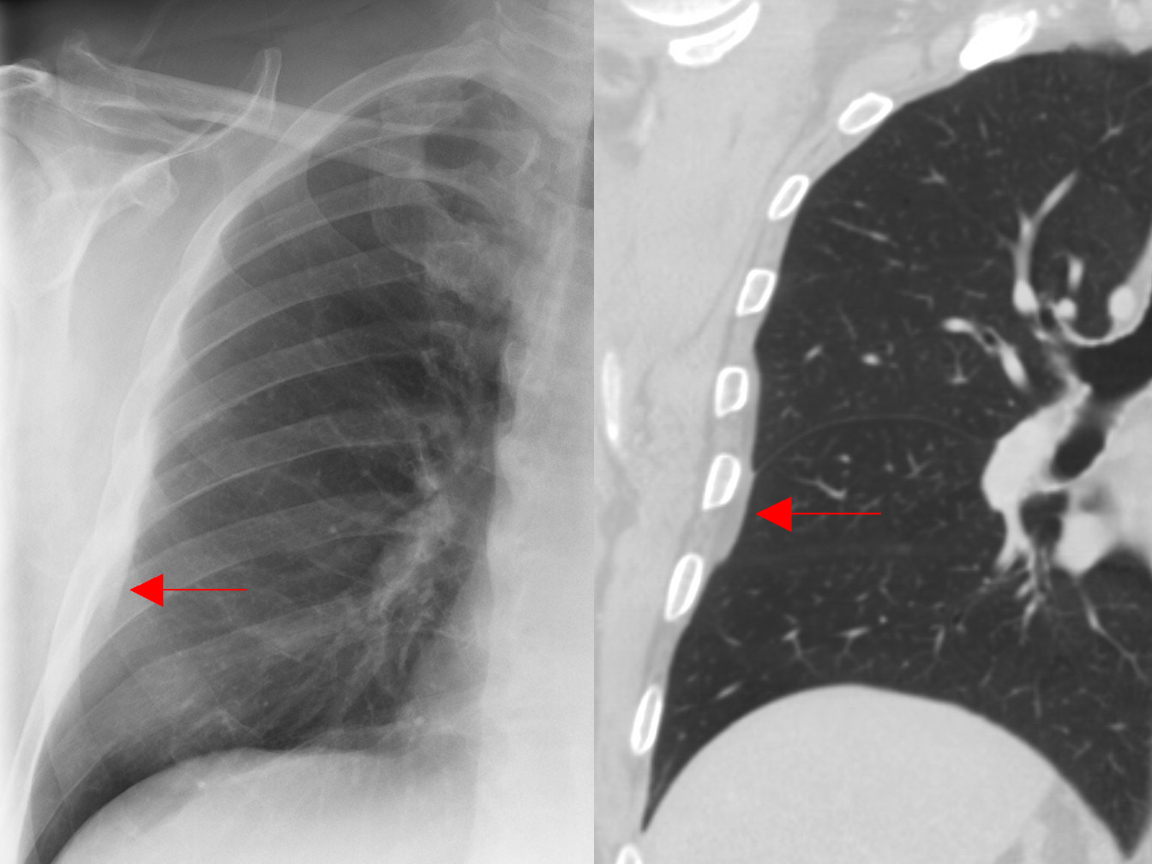

Gallery Pleural subpleural fat

subpleural fat